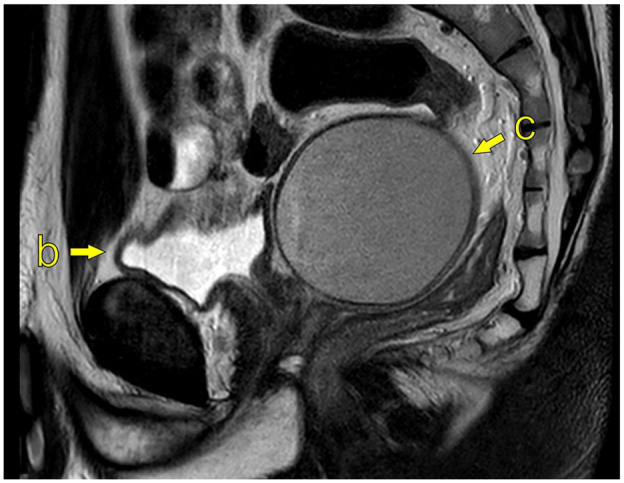

简介:Zinner综合征(ZS)以单侧肾脏发育不全、同侧精囊囊肿和射精管梗阻为特征。虽然罕见,泌尿科医生可能会遇到在他们的临床实践的某些点。文献主要局限于病例报告,对病情了解甚少。我们的目标是报告在两个中心管理的ZS病例,以便获得对这种情况的进一步临床见解。方法:对2021年1月至2024年6月期间在挪威西部两个中心出现的ZS病例进行回顾性分析。收集了有关人口统计学细节、症状学、影像学发现、管理和生育结果的数据。结果:6例患者符合ZS的全部三联征,年龄18 ~ 70岁。5例患者在出现症状时,报告诸如性活动中射精和睾丸疼痛等问题。两例急诊,一例急性尿潴留,另一例严重盆腔疼痛。半数患者采用保守治疗成功。三分之二的人通过自然受孕或辅助生殖方法生了孩子,而其余的人则接受了精子冷冻保存。结论:ZS表现出广泛的症状和不同的年龄。并非所有有症状的病例都需要手术干预,治疗应个体化。在某些情况下,保守的方法是可行的。

Introduction: Zinner syndrome (ZS) is characterised by unilateral renal agenesis, ipsilateral seminal vesicle cyst and obstruction of the ejaculatory duct. Although rare, urologists may encounter it at some point in their clinical practice. The literature is largely limited to case reports, and the condition is poorly understood. Our objective was to report on cases of ZS that have been managed at two centres in order to gain further clinical insights on this condition.

Results: Six cases were identified that met the full triad for ZS, with ages ranging from 18 to 70 years. Five patients were symptomatic at presentation, reporting issues such as anejaculation and testicular pain during sexual activity. Two cases presented as emergencies, one with acute urinary retention and the other with severe pelvic pain. Half of the patients were successfully managed with a conservative approach. Two-thirds had children, either through natural conception or assisted reproductive methods, while the remaining patients underwent sperm cryopreservation.